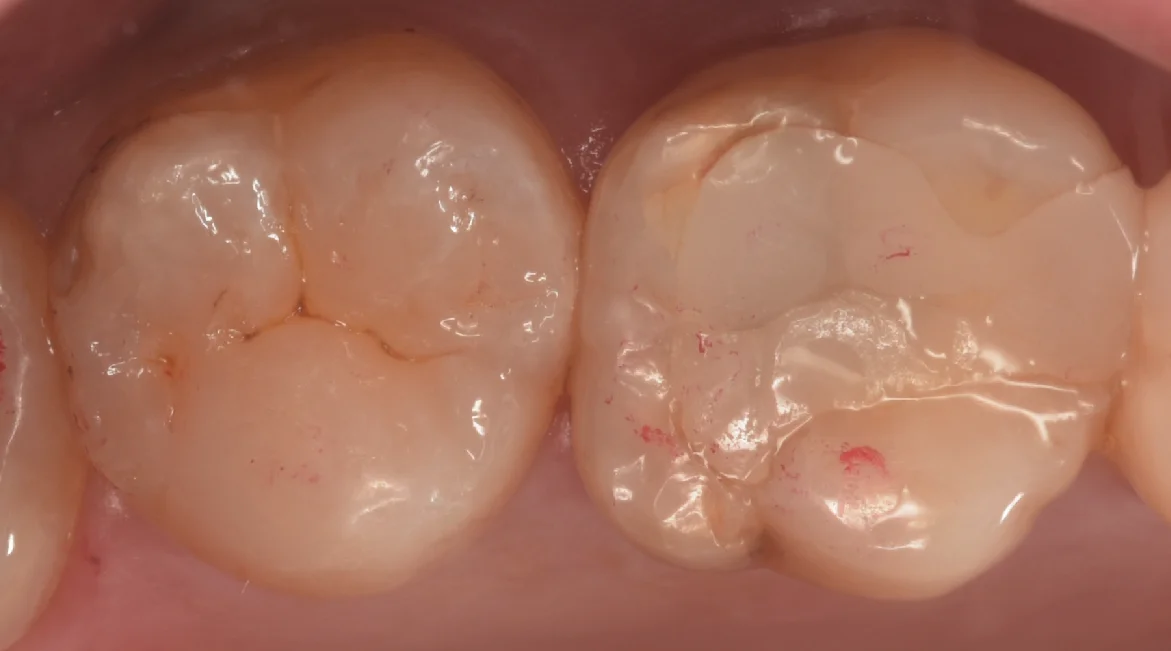

そして詰め終わったのがこちらになります。

どうでしょうか?

違和感なくしっかりと詰め終われたかと思います。

個人的にはかなり良い仕上がりになったと思います。

1週間経って歯の色があってくると拡大視野を使用した歯科医師が診ても一瞬わからないんじゃないでしょうか?!

治療の術前術後がこちらになります。